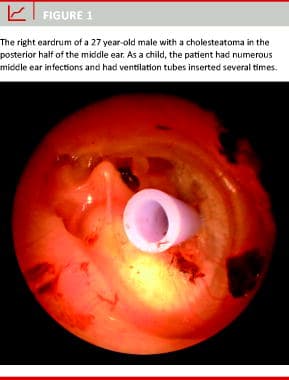

Cholesteatoma (Figure 1) can cause serious complications such as hearing loss, facial paresis, dizziness and intracranial infections. A cholesteatoma usually appears as a defect in the eardrum through which squamous epithelium grows into the middle ear or mastoid. Here, the choles-teatoma can destroy important structures such as the ossicles, the facial nerve, the vestibular organ and the cochlea, thus requiring meticulous surgical removal [1].